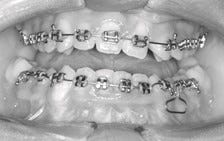

Zoals veel van hun leeftijdgenoten krijgen ook kinderen met schisis rond hun twaalfde jaar vaak een slotjes- beugel (ook wel vaste beugel of blokjesbeugel genoemd, zie foto hieronder).